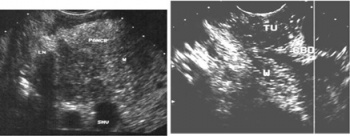

2.על-שמע (אולטרהסאונד) — בחולים הלוקים בשאתות בלבלב אפשר להדגים את השאת, וכן לראות את דרכי המרה (תצלום 23.9).

האולטרה-סאונד האנדוסקופי (EUS) מאפשרת לראות את השאת, את גודלה (איור 24.9);

האם פרצה לאיברים אחרים, תפסה כלי דם או מערבת בלוטות לימפה (תצלום 25.9).

בהכוונת ה-EUS אפשר להחדיר מחט לשאת או לבלוטה ולקחת בדיקה ציטולוגית מהם (תצלום 26.9).